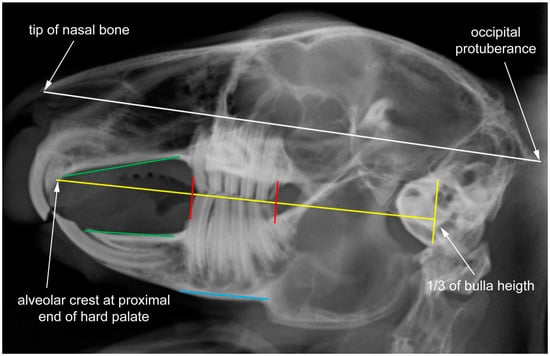

| LM | Type | Definition |

|---|---|---|

| 1 | II | most anterior point of nasal bone |

| 2 | I | intersection between second maxillary incisor (I2) (peg tooth) and maxillary bone |

| 3 | II | most anterior tip of first maxillary incisor (I1) |

| 4 | II | most anterior tip of first mandibular incisor (i1) |

| 5 | I | intersection between first mandibular incisor (i1) and mandibular bone |

| 6 | I | anterior intersection between mandible and first mandibular cheek tooth (p2) |

| 7 | II | most anterior point of occlusal plane between maxillary and mandibular first cheek tooth (P2, p2) |

| 8 | II | most posterior point of occlusal plane between maxillary and mandibular last molar (M3, m3) |

| 9 | I | posterior intersection between mandible and last mandibular molar (m3) |

| 10 | I | posterior intersection between maxillary bone and last maxillary molar (M3) |

| 11 | I | anterior intersection between maxillary bone and first maxillary cheek tooth (P2) |

| 12 | II | antegonial notch of mandible |

| 13 | II | most posterior dorsal point of angular process |

| 14 | II | most posterior point of occipital protuberance |